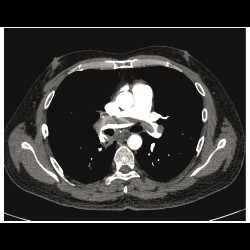

Acute pulmonary embolism being the first presentation of undetected HIV infection

Acute pulmonary embolism being the first presentation of undetected HIV infection

Acute pulmonary embolism being the first presentation of undetected HIV infection

Acute pulmonary embolism being the first presentation of undetected HIV infection